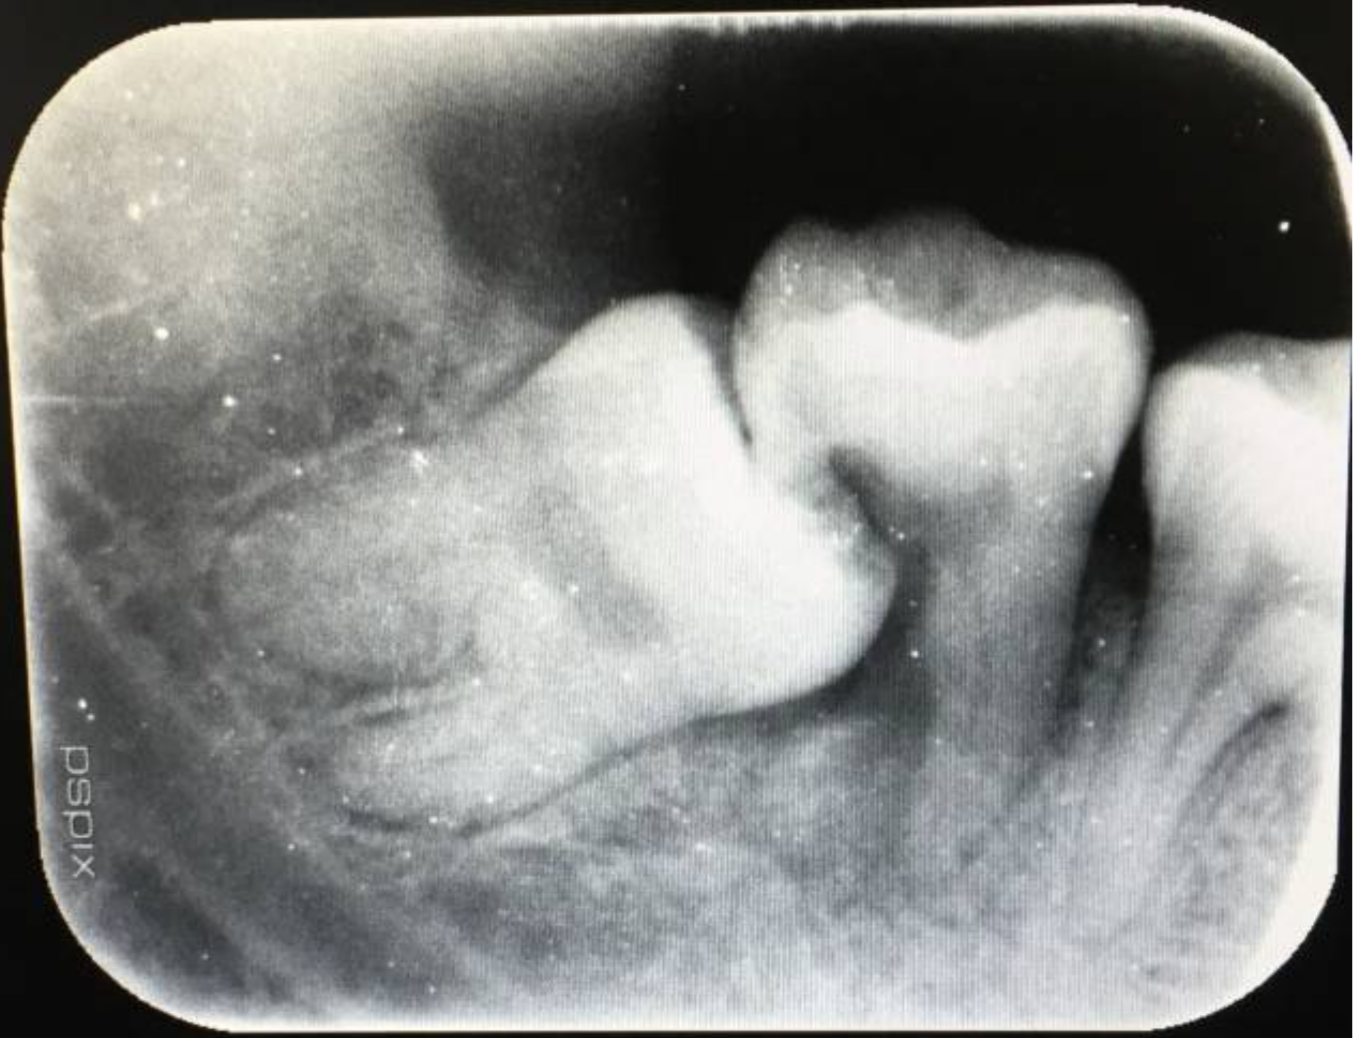

智齿拍片图

请问我这智齿要提前去拔么